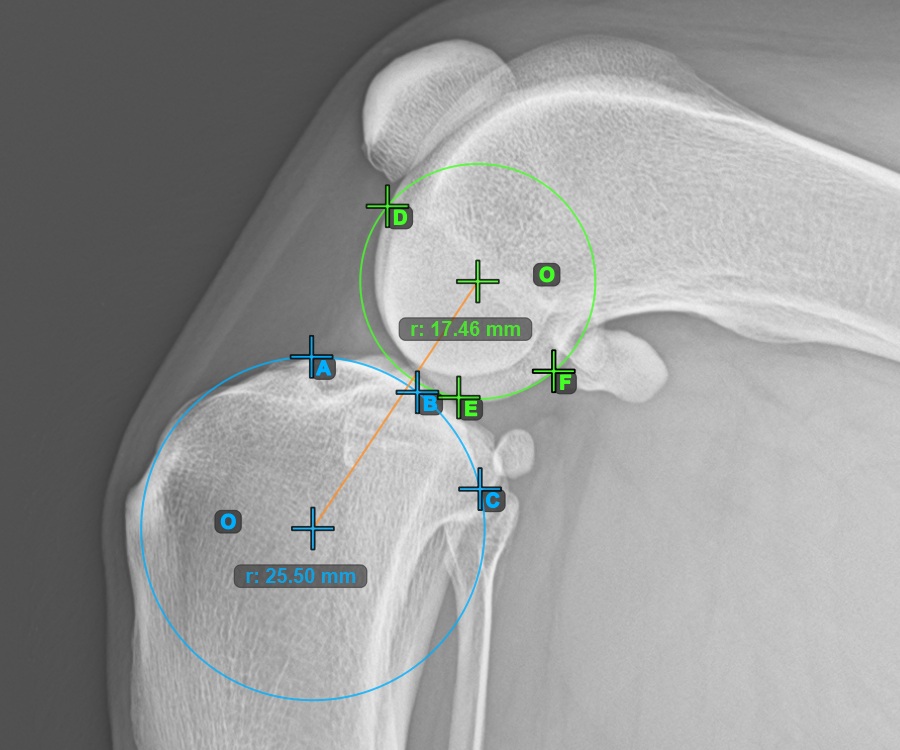

Ezen felül jelölje meg a három pontot a második Condylus Femoris ízületi felszínén.

Jelölje meg a három pontot a combcsont belső (másodlagos) condylusán (Condylus Femoris). A sorrendtől függetlenül ügyeljen arra, hogy megjelölje a legfelső pontot, a legalacsonyabb pontot és a Condylus Femoris középpontját. A három pont alapján a rendszer automatikusan létrehoz egy kört.

A lenti kép a második Condylus Femoris-on elhelyezett három pont tipikus elhelyezkedését ábrázolja.

Jelöljön meg egy pontot az ízület előtt a két fő condylus kör közötti közös tangensen. Egy vonal automatikusan áthalad a megjelölt ponton.

A lenti kép a két kör közötti közös tangensen elhelyezett pont tipikus elhelyezkedését ábrázolja.